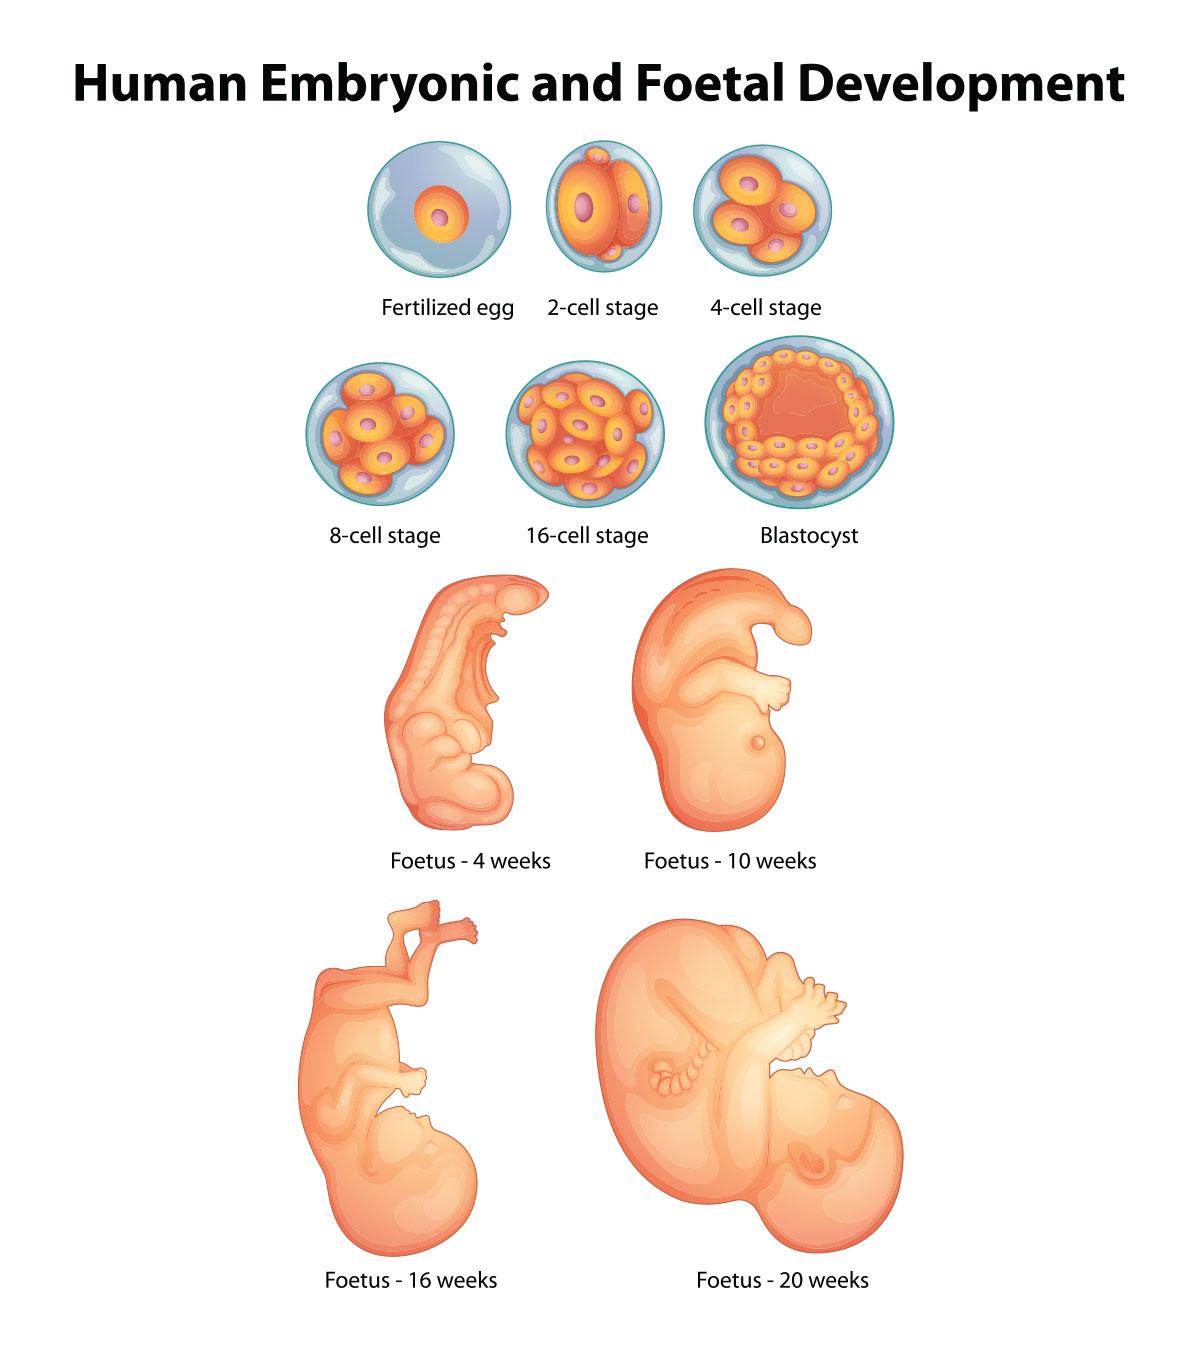

Looking for captivating what does a 2 month old fetus look like images? All, in collaboration with felix.edu.vn, presents a curated selection. Dive into the details for more.

what does a 2 month old fetus look like

Posts: what does a 2 month old fetus look like